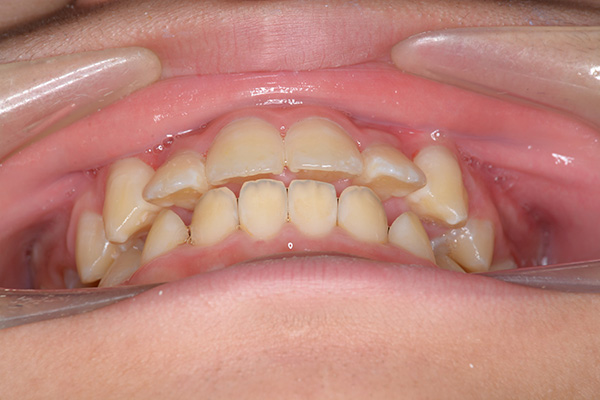

| 顔貌所見 | 正貌はほぼ左右対称。側貌はconvex type、口唇閉鎖不全、口元の突出感が認められた。 |

| 口腔内所見 | over jet 5.5mm,over bite 5.0mm,大臼歯関係はⅠ級 、Hellmanのdental ageはⅢBであり上突歯列を呈していた。 |

| セファロ所見 | Sellaに対して下顎頭は後方位だが下顎骨は大きくしっかりとした形態をしており前後的にはⅠ級、垂直的にはロウアングルの骨格形態をしていた。 上顎前歯は唇側傾斜を呈していた。 |